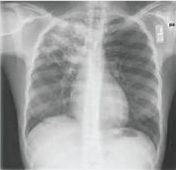

Active primary pulmonary tuberculosis is a disease of infancy, or young adult when they are not exposed to the Mycobacterium TB bacilli. It may manifest as pneumonic consolidation (homogenous dense opacity or patchy opacification mostly in middle and lower lobes with or without hilar lymphadenopathy called Ghon complex. Other radiological features of active primary TB are either miliary opacities or pleural effusion or pulmonary oedema (Kerely B line) (Figure 1-6) [12,13].

Figure 1: Chest x-ray showing dense homogenous opacity in right, middle and lower lobe of primary pulmonary TB. View Figure 1